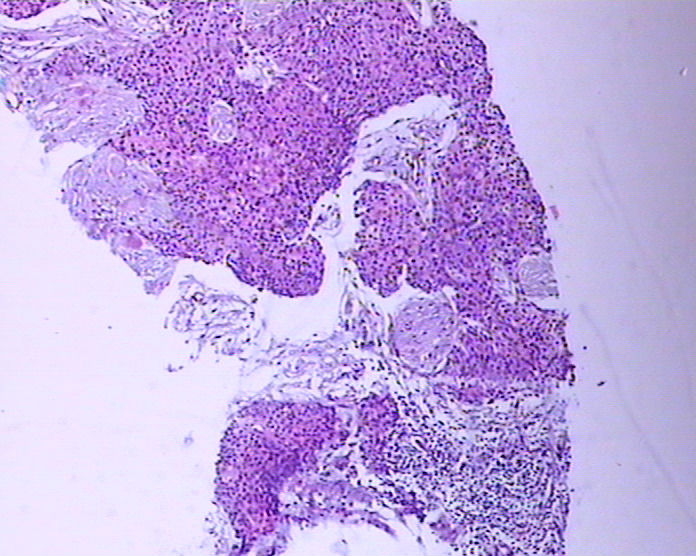

患者男性,51岁,发现右纵膈肿物,行穿刺活检。

参考诊断

鳞癌?

1。胸腺癌?

2.低分化鳞癌?

胸腺癌?